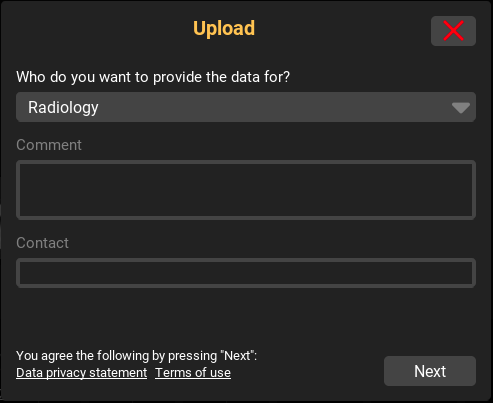

9.1.1. DICOM Upload

Sofern der Upload serverseitig aktiviert wurde, können Sie mit dem "+"-Button oder mittels Drag’n’Drop (Reinziehen von Dateien in die Inbox) DICOM Daten auf den Server hochladen. Bei Nutzung des "+"-Buttons erscheint vorher ein Dialog zur Auswahl der Upload-Daten. Sollten mehrere Upload-Ziele (bspw. Abteilungen) für Sie zur Verfügung stehen, erscheint ein weiterer Dialog. Über diesen können Sie sowohl das Upload-Ziel auswählen als auch bei Bedarf weitere Angaben zu Ihrem Upload machen. Nach Bestätigung aller Angaben, werden die Dateien auf den Server hochgeladen. Sobald die Daten erfolgreich hochgeladen und serverseitig importiert wurden, erscheinen diese in Ihrer Inbox für die Bild-Anzeige. Des Weiteren befindet sich in jeder hochgeladenen Studie ein Upload-Bericht. Dieser fasst alle Upload-Information (Uploader, Datum, Anzahl Dateien, manuelle Angaben, etc.) noch einmal zusammen und protokolliert diese.